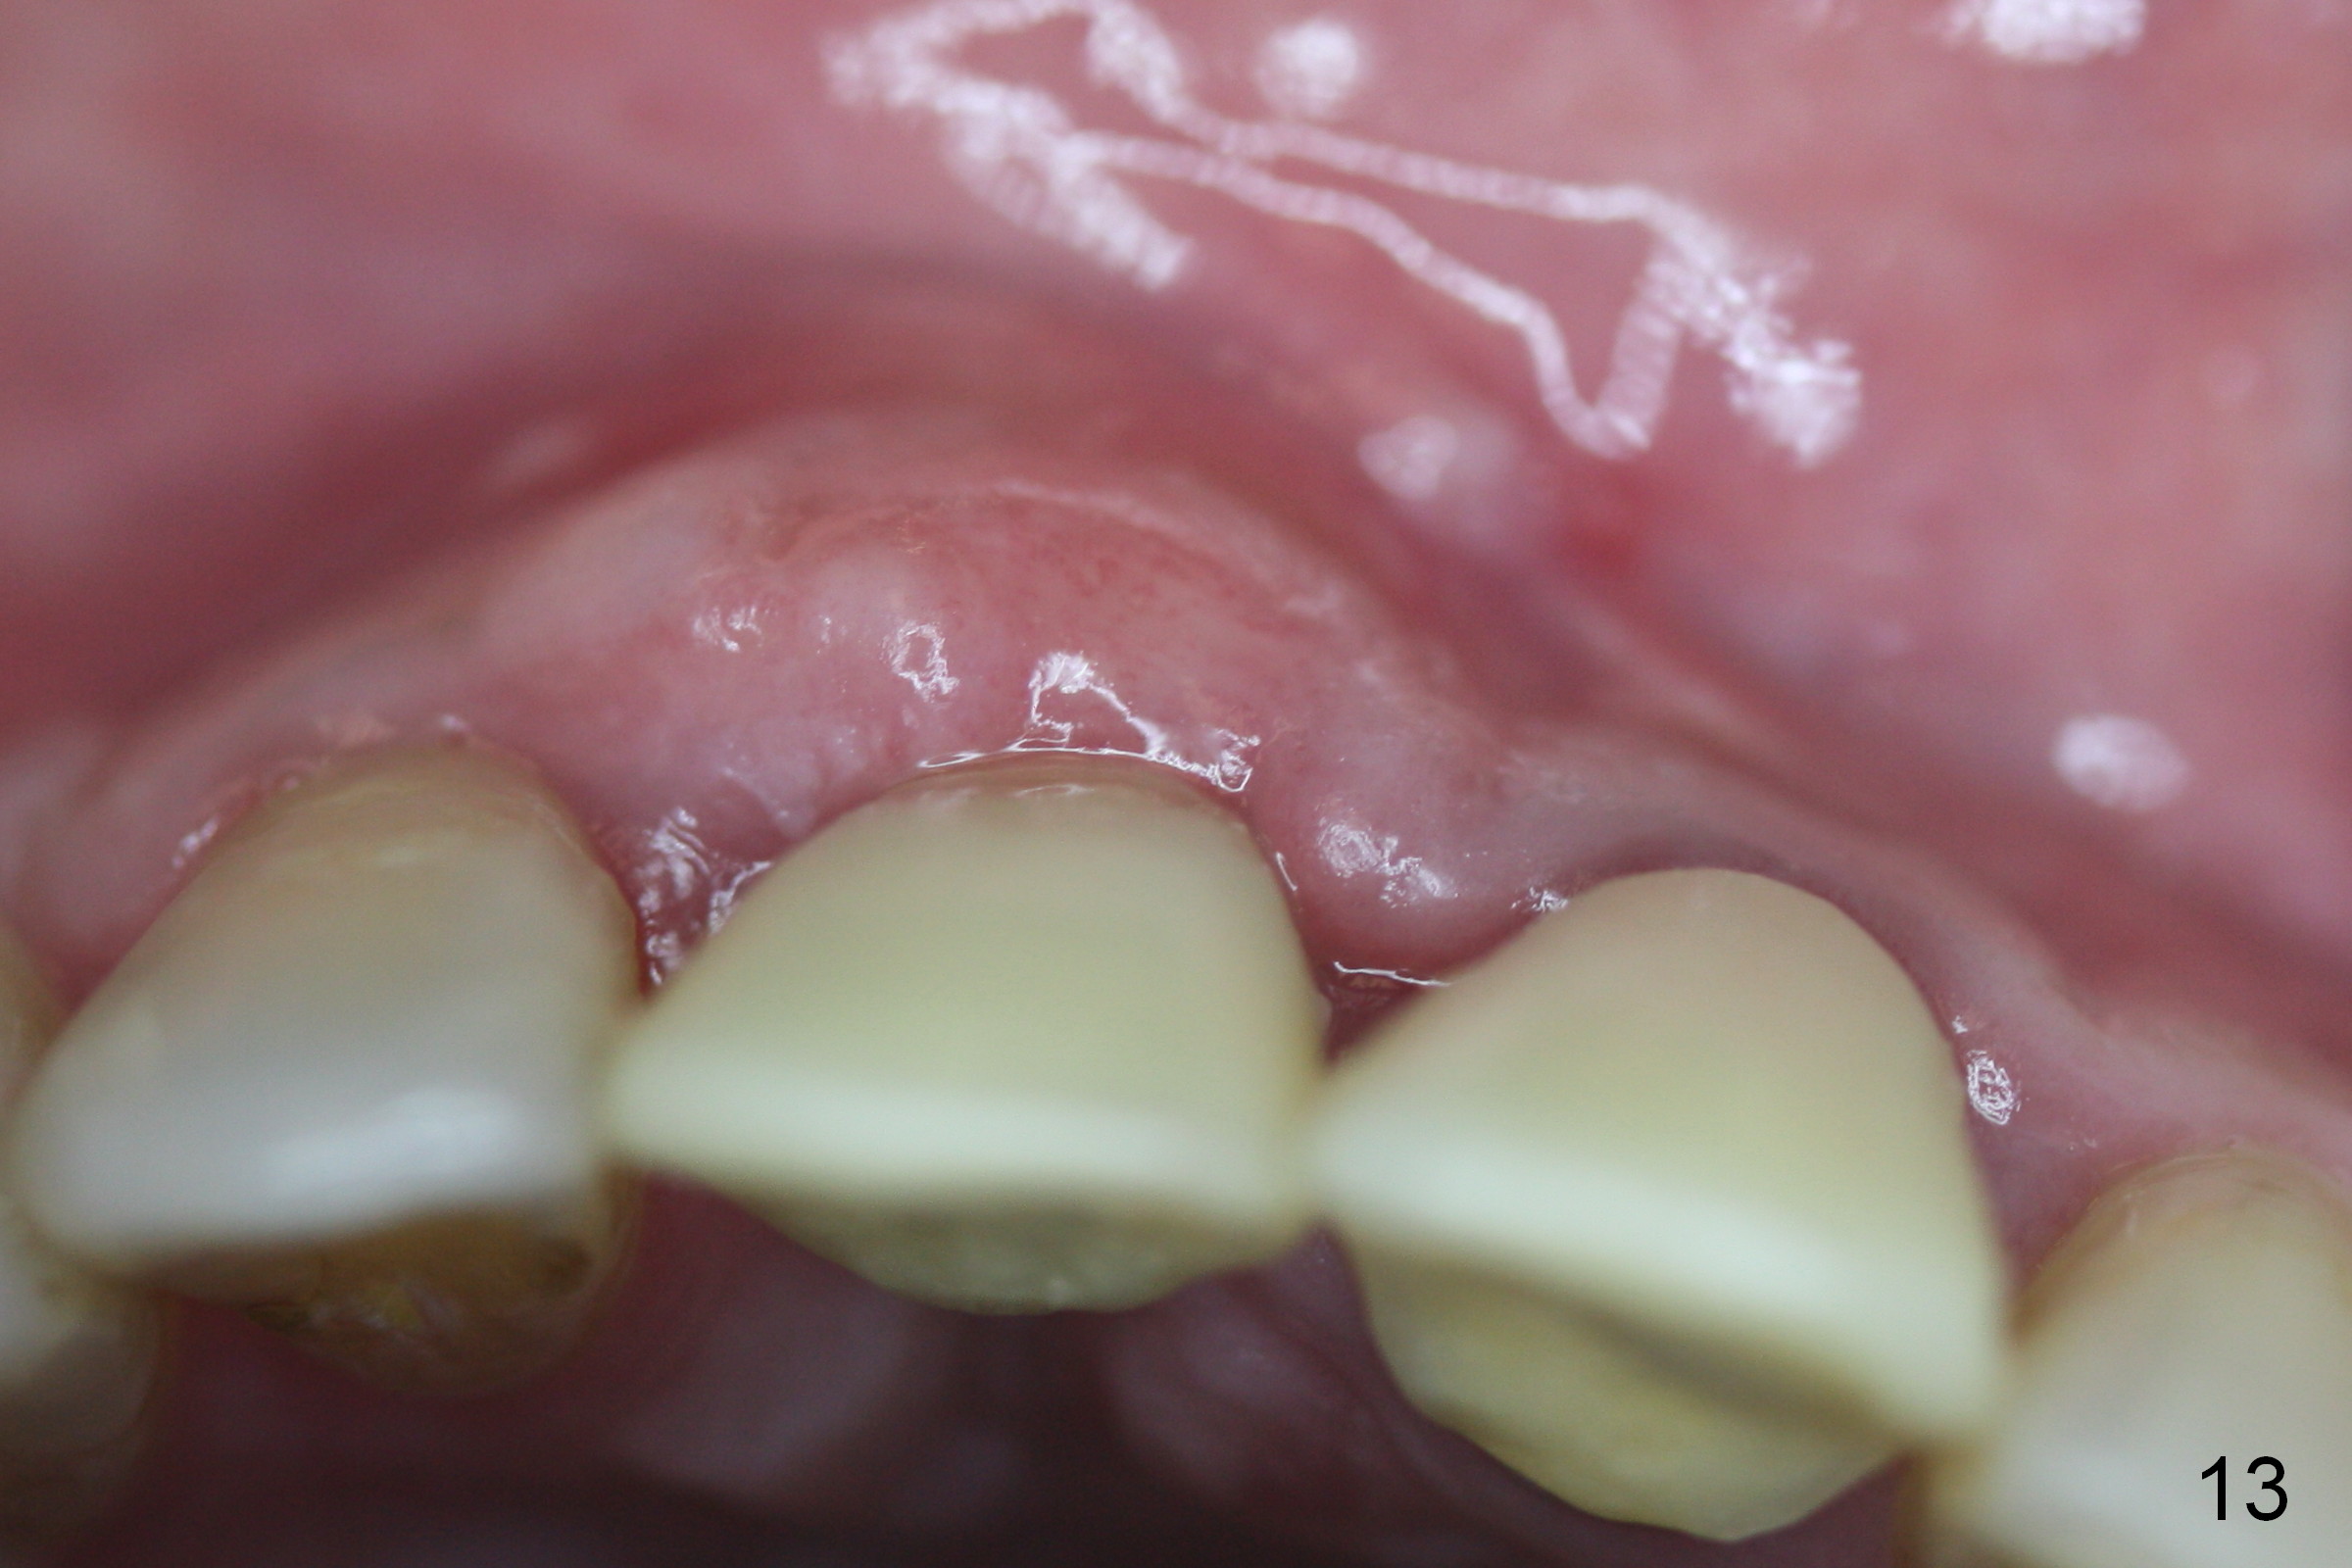

To correct the gingival margin associated with #8 implant, bone graft is needed.  Particulate graft may not stay in place. Chin graft is harvested.  Since the roots of the lower anterior teeth are long (Fig.8), the width of the chin graft is limited for direct screw fixation (Fig.9,10).  Titanium mesh is used for fixation of the graft.  Connective tissue graft from the palate is to increase bulk at the site of #8 (Fig.11 *).  There is no symptom or sign of infection 1 month postop (Fig.12,13).  Although there is alteration of sensation of the lower incisors, there is no apical radiolucency of them 4 months postop (Fig14).  There is no abnormality associated with the bone graft and Titanium mesh (Fig.15).

Nine months postop, the gingival margin is symmetrical over the provisional crowns at #8 and 9 (Fig.16).  There is no bulging or concavity associated with the implant at #8 (Fig.17).  Screw (Fig.16 <) removal is scheduled prior to final restoration.  The gingiva is healthy 1 year 7 months post cementation (Fig.18).